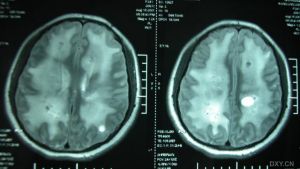

張量成像檢查1、腦缺血(cerebral ischemia)

腦血流下降到低於10~15 ml/100 g/min時將導致細胞內水容量增大,水從細胞間隙流入細胞內使細胞腫脹,產生細胞毒性水腫。使用傳統MR,急性期腦梗塞很難被發現,缺血腦實質的範圍只有在較晚的時期當血管源性水腫出現時才能被發現。當普通MR表現正常的時候,DWI和DTI可以早期發現急性腦梗塞。他們使鑑別腦梗塞急慢性期的改變成為可能,這對治療方法的選擇具有重要的臨床價值。在急性期,局灶性腦梗塞發作30分鐘內,ADC值最初下降約30~50%,在急性和亞急性早期,梗塞灶的白質比灰質的ADC值下降的更明顯。對缺血性腦梗塞,DTI的參數如MD,最初是下降,然後升高,最後比正常高。在損傷的慢性期,ADC一直保持升高。在ADC先下降後升高的間隔期,有段時間是ADC值表現正常,這個期間就是所謂的“假正常期”。在成人,這個時期大約在腦梗塞9天后,而在新生兒大約在7天后。除了ADC的變化,在缺血早期梗塞灶腦白質的FA值會有一個急性升高。這個急性升高后,緊接著在慢性期FA值會明顯的下降。這種變化被認為是由於細胞結構的破壞導致組織微觀結構正常順序的喪失。

在腦梗塞慢性期,相對於ADC的重新正常化,和隨後的升高,彌散各向異性指數FA值明顯的低於對側相同區域正常腦組織,即使是在缺血性腦梗塞2-6個月後梗塞灶的FA值依然低於健側。ADC閾值在預測組織存活和缺血性腦梗塞預後方面可能具有重要價值。ADC和各向異性參數的結合,能很好的明確缺血性腦梗塞的臨床分期。